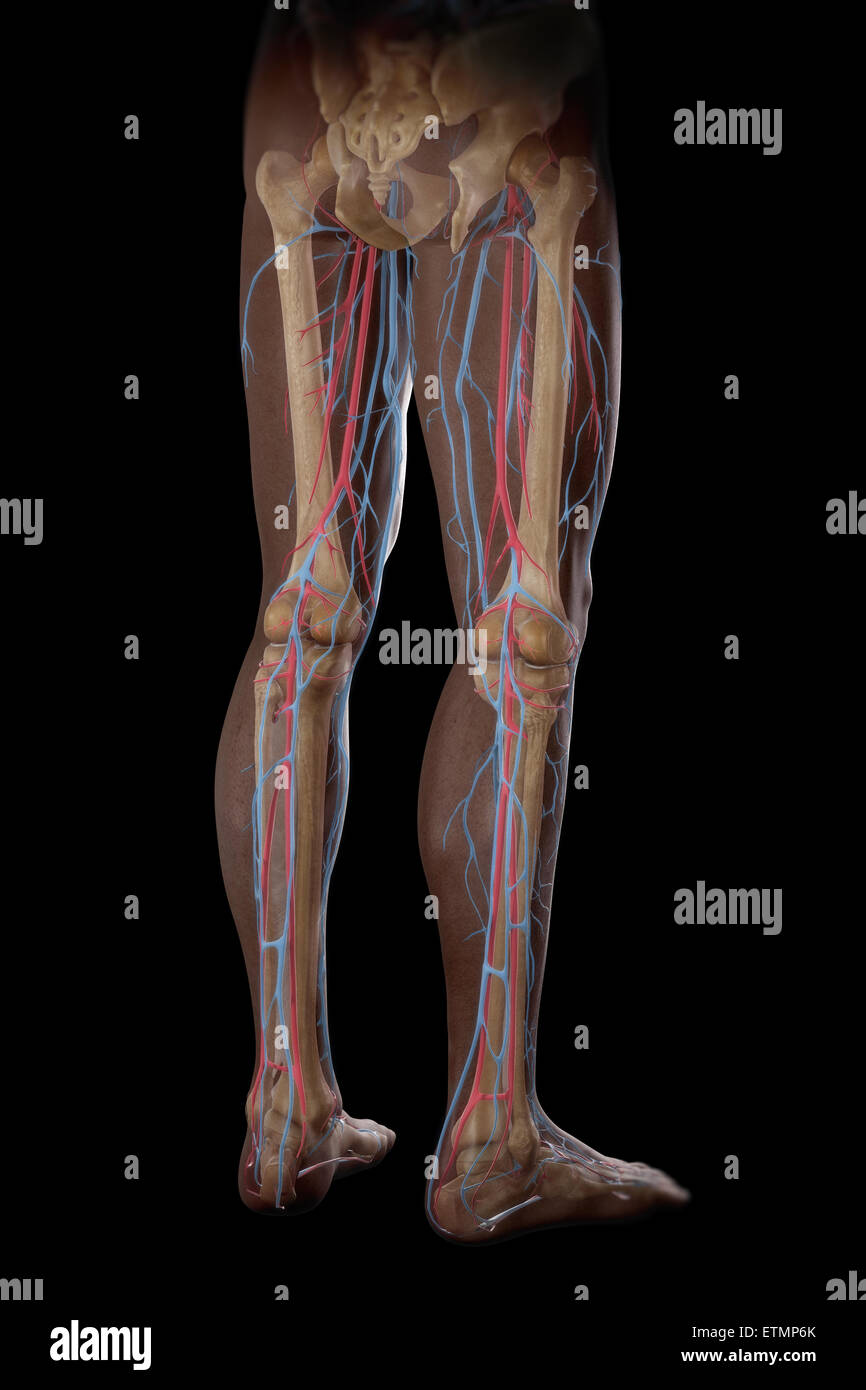

RF2KDED11–Arterielle Versorgung des vorderen und hinteren Beins über die Arteria poplitealis und ihre Zweige

RMETMN27–Darstellung der Blutversorgung und Skelett-Struktur der Unterschenkel, durch die Haut sichtbar.

RMETMNMF–Darstellung der Blutversorgung und Skelettsystem an den Unterschenkeln, durch die Haut sichtbar.

RMETMP9E–Darstellung der Blutversorgung und Skelett-Struktur der Unterschenkel, durch die Haut sichtbar.